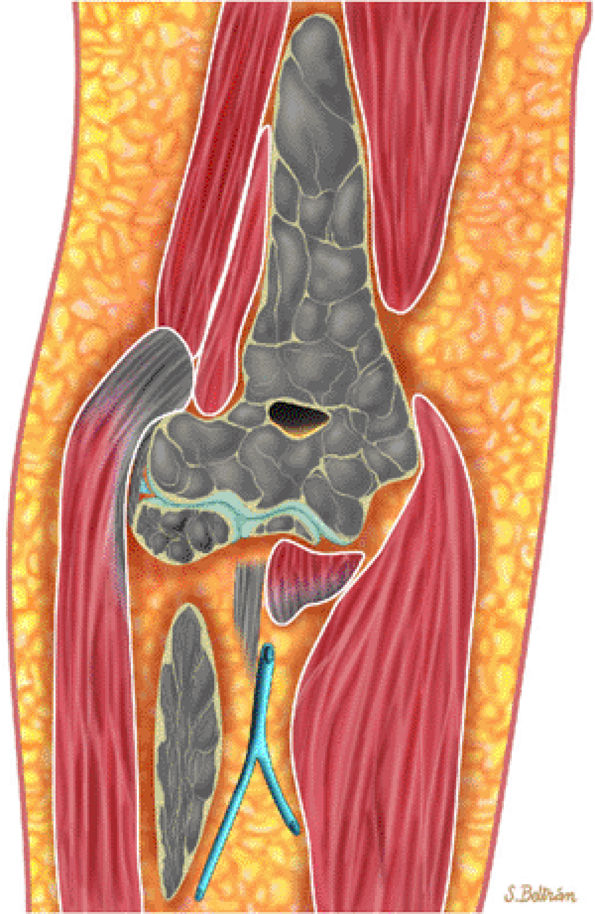

![]() |

FIGURE 13.9 ● Sagittal graphic illustration shows diffuse leukemic bone marrow infiltration of the lumbar spine (shown in brown).